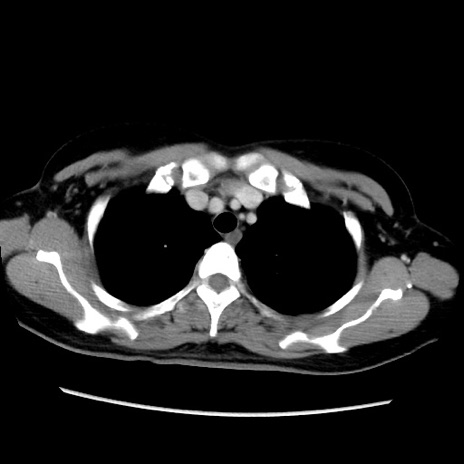

症例39(横断像)

【症例】40歳代女性

【主訴】上下腹部痛

【現病歴】2日目から下腹部痛あり。夜間は痛みで眠れなかった。昨日より上腹部痛と下痢が出現。臥位で痛みは軽快したため、休んでいた。本日になって臥位でも立位でも痛みが強くなってきたため救急要請。

【既往歴】子宮内膜症

【身体所見】部:平坦・軟、左上下腹部に圧痛あり、反跳痛あり。

【データ】WBC 21800、CRP 26.78